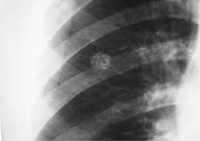

Диагноз гамартомы легкого устанавливают по данным рентгенографии, КТ и МРТ легких и трансторакальной пункционной биопсии с гистологическим исследованием биоптата. На рентгенограмме и томограмме гамартома легкого визуализируется обычно как одиночная небольшая (редко 2-4 см) округлая тень периферической локализации с резкими и четкими контурами на фоне неизмененной легочной ткани. Поверхность опухоли может быть гладкой или бугристой. Интенсивность тени гамартомы легкого зависит от размера узла и содержания известковых включений.

Выделяют несколько рентгенологических вариантов гамартомы легкого - тени средней интенсивности и гомогенной структуры; неоднородные тени средней интенсивности с обызвествлением; неоднородные тени средней интенсивности со слоистым обызвествлением/уплотнением в центре и неоднородные тени высокой интенсивности с массивной инкрустацией. При больших размерах гамартомы легкого (4 - 5 см) может появиться усиление легочного рисунка за счет сближения между собой сосудистых и бронхиальных ветвей.